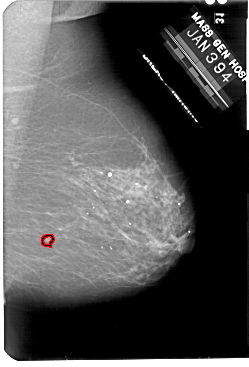

A_1901_1.LEFT_CC

LEFT_CC LINES 5491 PIXELS_PER_LINE 3631 BITS_PER_PIXEL 12 RESOLUTION 43.5 NON_OVERLAY

FILE: A_1901_1.RIGHT_CC.OVERLAY

TOTAL_ABNORMALITIES 1

ABNORMALITY 1

LESION_TYPE MASS SHAPE IRREGULAR MARGINS ILL_DEFINED

ASSESSMENT 4

SUBTLETY 5

PATHOLOGY MALIGNANT

TOTAL_OUTLINES 1

BOUNDARY